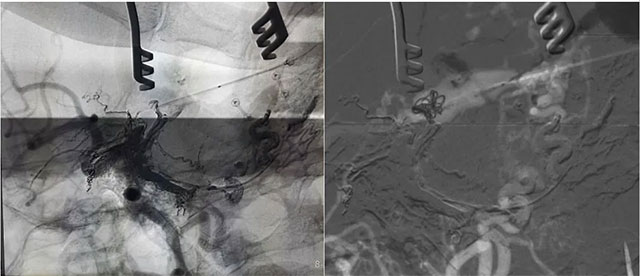

經(jīng)左側(cè)股動(dòng)脈以單彎造影管超選至左側(cè)頸總動(dòng)脈造影明確靜脈穿刺點(diǎn)入路,予以穿刺針穿刺成功后造影明確在位,隨后 Echelon 10微導(dǎo)管到位橫竇,填入一枚彈簧圈做塞子,造影明確位置后,緩慢注入 Onxy18膠 5毫升,鑄膠彌散良好,通過靜脈逆向彌散至部分供血?jiǎng)用}內(nèi)。復(fù)查造影,見瘺口完全被栓塞,引流靜脈消失,手術(shù)成功。

術(shù)后患者臨床癥狀消除,精神矍鑠,現(xiàn)正在康復(fù)中。

▲ 術(shù)后影像